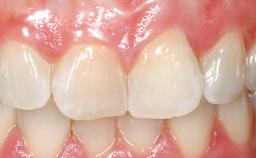

Late Flapless Placement of an Implant in a Maxillary Left Central Incisor Site

Prosthesis Type FDP

Loading Protocol Conventional or early

Retention Cemented, with prosthesis margin < 3mm submucosal Cemented, with prosthesis margin < 3mm submucosal

Provisional Implant-Supported Prosthesis Prosthodontic margin < 3 mm apical to mucosal margin Prosthodontic margin < 3 mm apical to mucosal margin

Soft Tissue Contour and Volume Slightly compromised